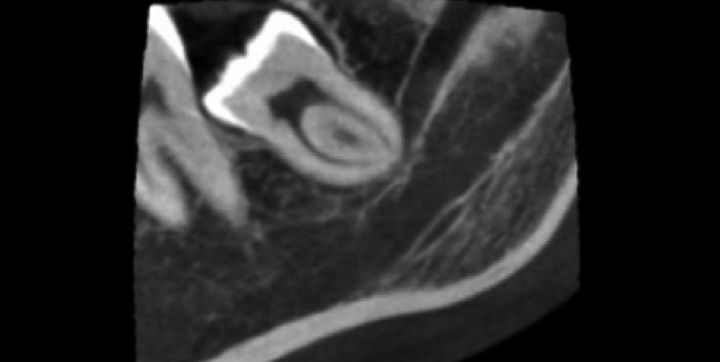

Såfremt nervekanalens kortikallamel mangler ud for rodens overlap, angives en risiko for midlertidig eller permanent nerveskade på 11,8-30 % (fig. 1 og 2). En formørkning af roden ud for kanalen eller en ændring i dens volumen og forløb (oftest indsnævring) er andre indikationer for umiddelbar relation mellem nerve og rod (2). Hyppigheden af tandens umiddelbare relation til nerven er størst, når kanalen ligger oralt for tanden, mindre ved beliggenhed lige under tandens rodspidser, og mindst hvor kanalen er beliggende bukkalt for tanden. På alle konventionelle 2D røntgenbilleder, der viste overlap af kanalen, kunne der ved 3D cone beam optagelser konstateres en fuldstændig adskillelse mellem nervus alveolaris inferior og tanden i 33 % af tilfældene.

Når tanden overlapper canalis mandibularis, er det altså vigtigt at konstatere ved supplerende undersøgelser, hvorvidt tanden er i umiddelbar relation til nervus alveolaris inferior Her er en 3D cone beam optagelse indiceret.